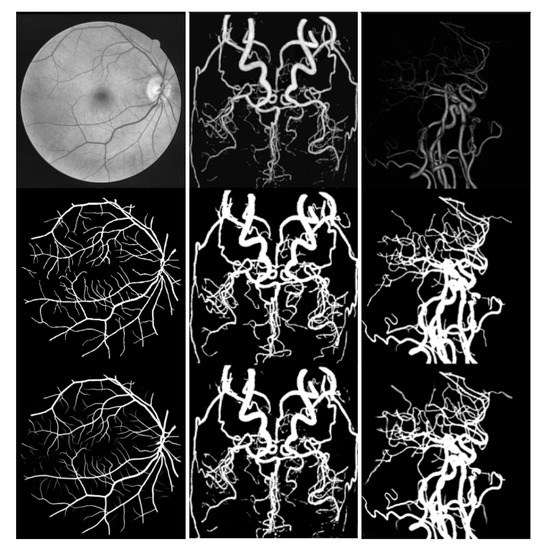

- We construct two brain vascular data sets, which uses multiple angles of CTA and MRA images from various patients, called the ELE and CORO data sets, respectively. The labeling process consults brain vascular experts.

- We perform experiments on the public retinal vascular data set DRIVE [4] and brain vascular data sets ELE and CORO, compare the results with the state-of-the-art methods, and obtain high accuracy. The effects of de-normalized structure on vascular segmentation were tested on DRIVE, ELE, and CORO data sets, respectively.